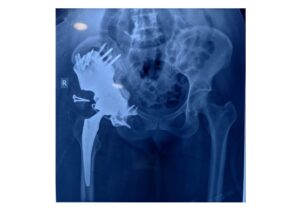

Postoperative Outcome: Stable Fixation and Anatomical Restoration

The custom pelvic implant (the FTL Cup) was successfully implanted following tumor resection, achieving stable fixation and accurate reconstruction of the acetabular region.

The implant demonstrated an excellent anatomical fit, restoring pelvic structure and enabling secure placement of the cemented acetabular component.

Early postoperative assessment indicated stable implant positioning and favorable conditions for functional recovery.